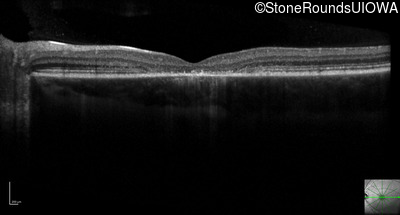

Optical Coherence Tomography - Right - 20/80 -1

Exemplar / OCT Stack